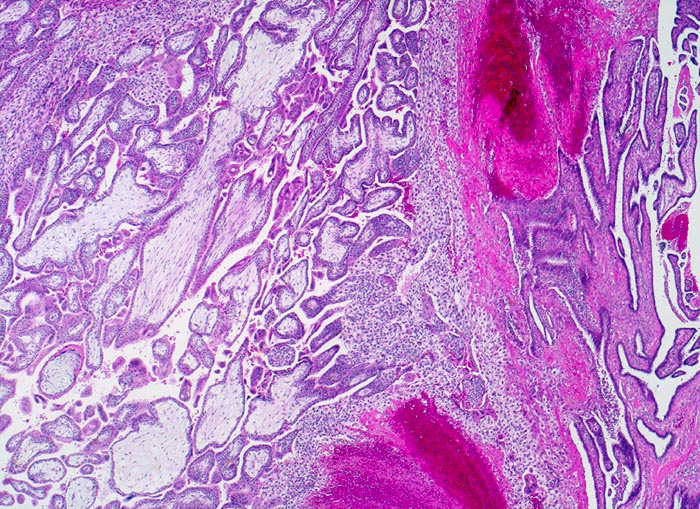

PathoPic ID 3871 - Tubargravidität

Tubargravidität

Tuba uterina

Genitalorgane, weiblich

Rechts im Bild Tubenschleimhaut. Links im Bild Dezidua und Plazentarzotten aus Frühschwangerschaft.

Extrauteringravidität

Histologie

25